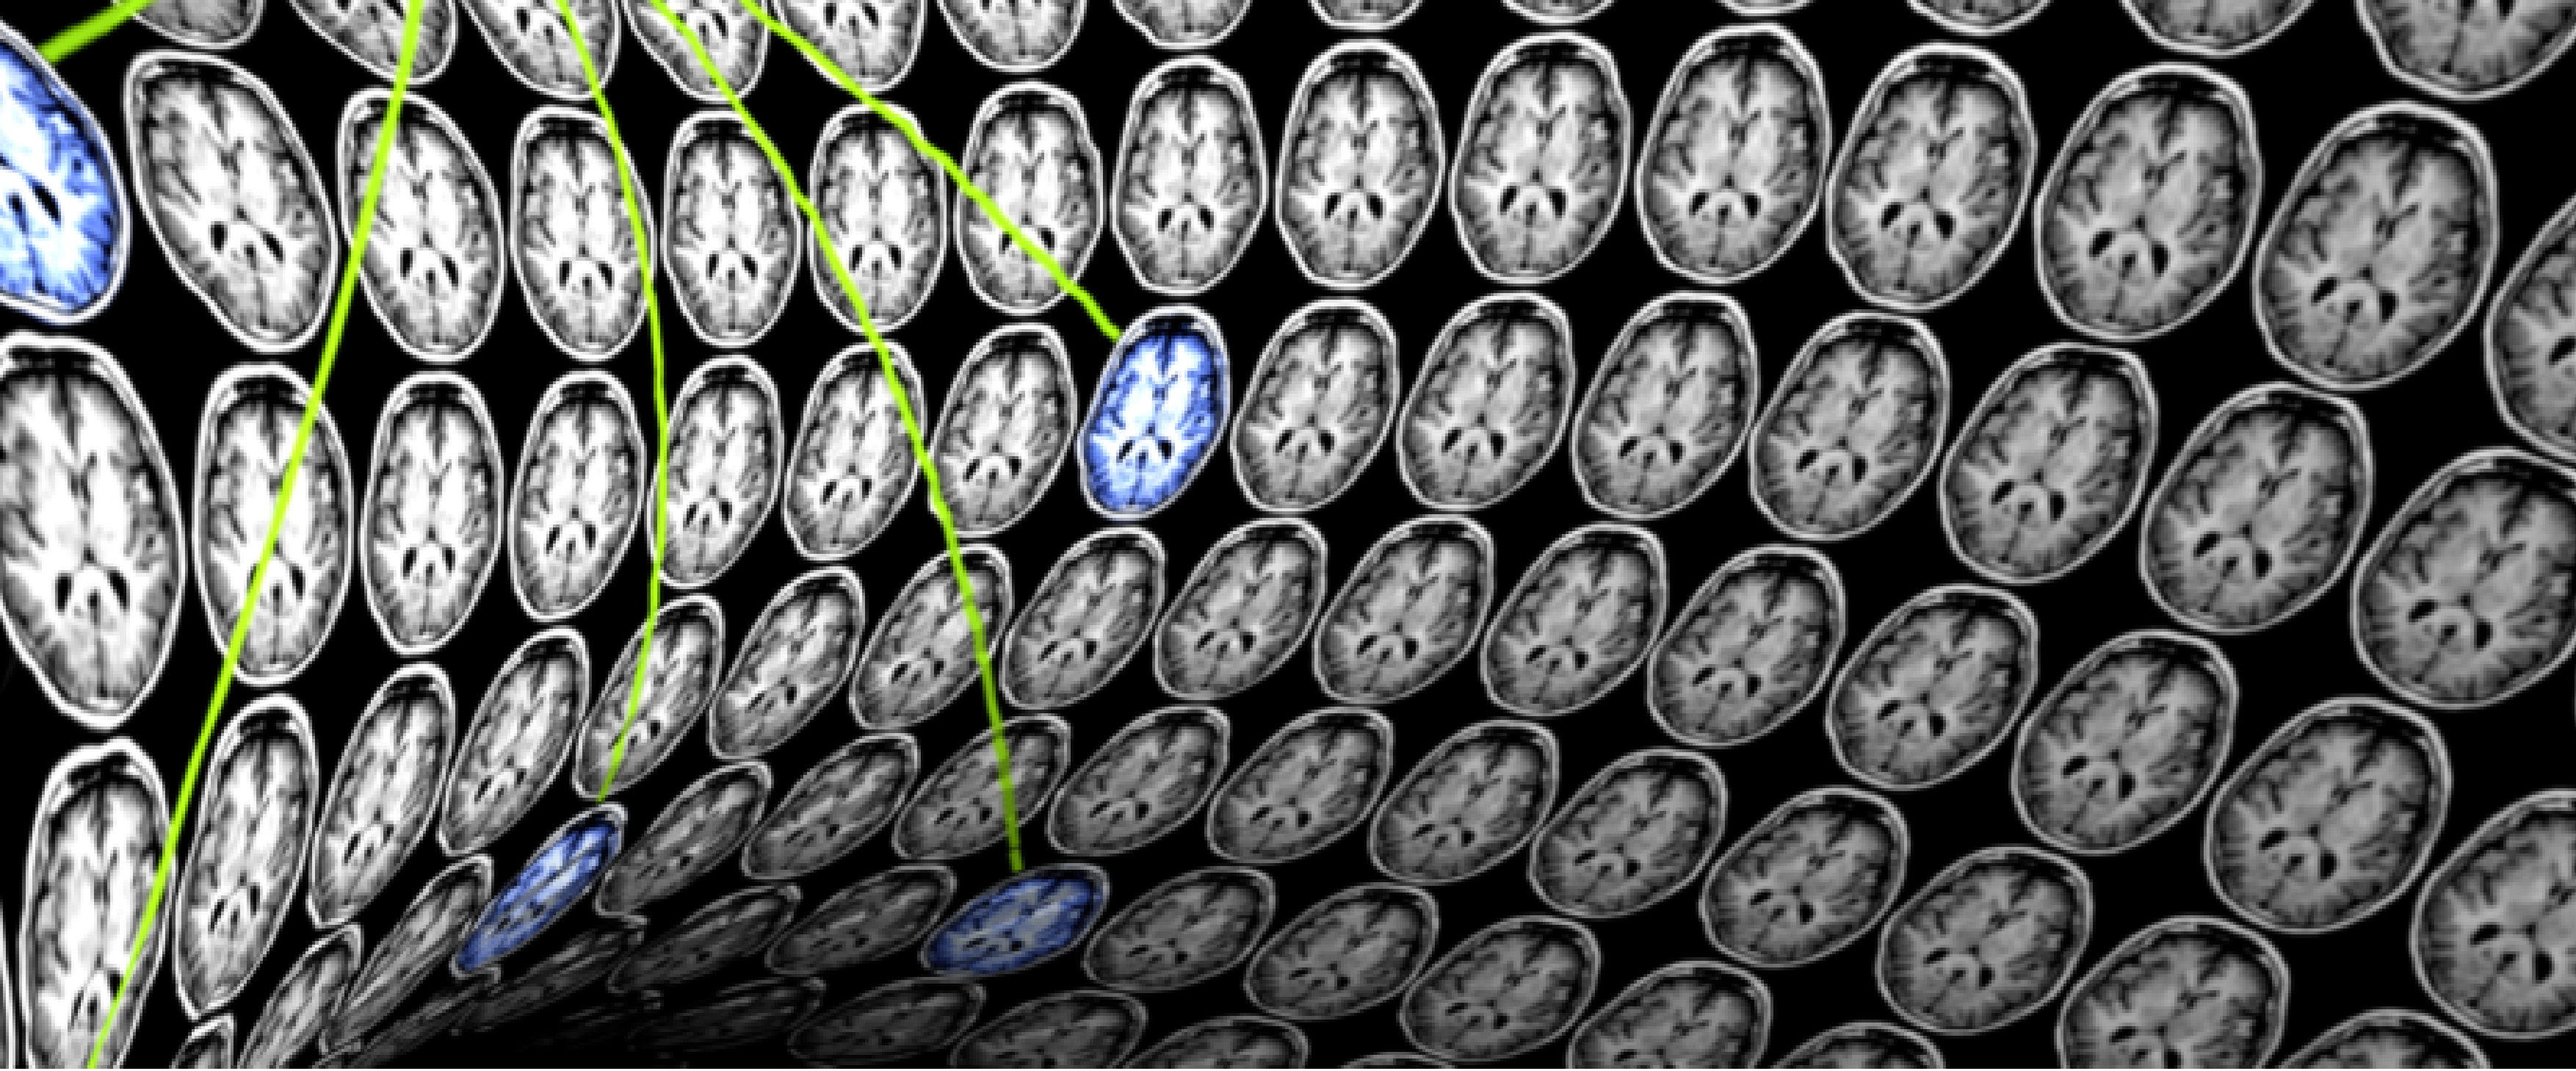

La Semaine du Cerveau 2020 à Neurospin

Du 16 au 20 mars 2020 @ Neurospin - 91190 Gif-sur-Yvette

La Semaine du Cerveau a pour but de sensibiliser le grand public à l'importance des recherches dans le domaine des neurosciences. Parmi les experts intervenants, Bertrand Thirion, directeur de l'équipe Parietal Inria / CEA et directeur de l'Institut DATAIA.

3e colloque sur l’imagerie médicale à l’heure de l’intelligence artificielle

22 avril 2020 @ Institut du Cerveau (ICM) - 75013 Paris

Ce colloque, soutenu par l'Institut DATAIA, est dédié aux algorithmes en médecine. Ses deux centres d’intérêt principaux sont l’analyse automatique des images médicales et la collecte et l’analyse de grandes données, désormais permises par l’informatisation du suivi des patients.